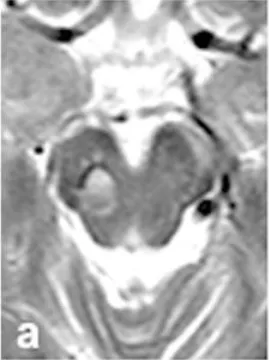

MRI检查提示存在轻微再出血(图a),令人惊讶的是患者当时仍无任何明显症状。这种"无症状性出血"是脑干海绵状血管瘤的典型特征,也是其危险性的重要体现。